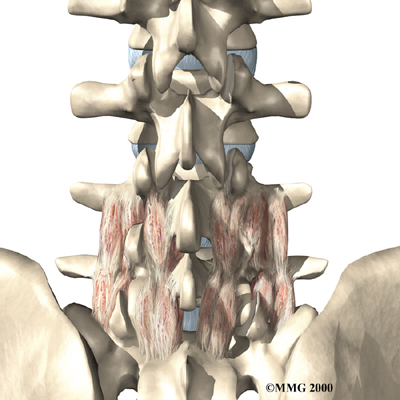

Surgeons perform this procedure through an incision in the low back. The incision reaches to the , the bony projections off the back of the vertebrae. The surgeon must move aside the muscles along the spine, called the paraspinal muscles. The fusion itself involves the lamina bone, the protective roof over the back surface of the spinal cord. In some cases, the surgeon may enlarge the neural foramina, the tunnels where the nerve roots leave the spinal cord.

Muscle Disruption

During the operation, the surgeon lifts off the small muscles that run along the back of the spinal column. Some of the nerves going to the muscles are cut. Lifting the muscles away from the bone impairs the blood supply to the muscles. Disruption of the nerve and blood supply can cause the muscles to fatigue easily, especially during a long work day and with heavy or repeated lifting. Exercises designed by a Chiropractor boost strength and endurance in the nearby muscles, reducing symptoms from this problem.